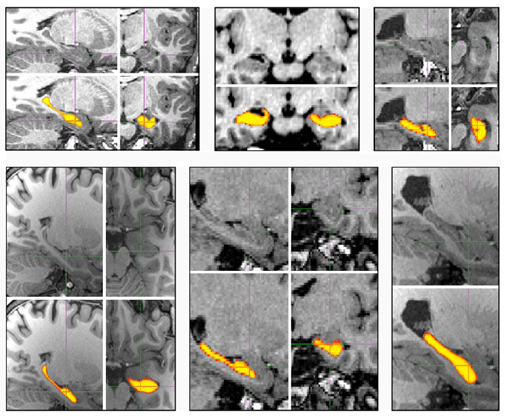

これまでは、脳ドックを受けても「あなたの脳の萎縮リスクは、目で見ただけでは分かりません」というのが現実でした。この大きなギャップを埋めるため、東北大学 瀧研究室は画像AI解析のトップ研究者らと海馬などの体積を高精度かつ高速で解析するAI技術(※1)を開発しました。

この技術の信頼性は、権威ある国際的な学術雑誌への掲載だけでなく、オックスフォード大学の研究チームによる検証でも証明されています。世界を代表する10のAI技術の中で、「すべてのデータセットで優れた性能を示し、信頼性、精度、効率の点で特に魅力的」という最高レベルの評価を得ています(※2)。

AIが海馬(黄色箇所)を高精度かつ高速解析

※1:国際論文誌でのAI技術の名称は “Hippodeep”。B Thyreau, Y Taki et. al., 2018、※2:Sghirripa S et. al., 2025(オックスフォード大学・豪州アデレード大学の研究チーム)ほか